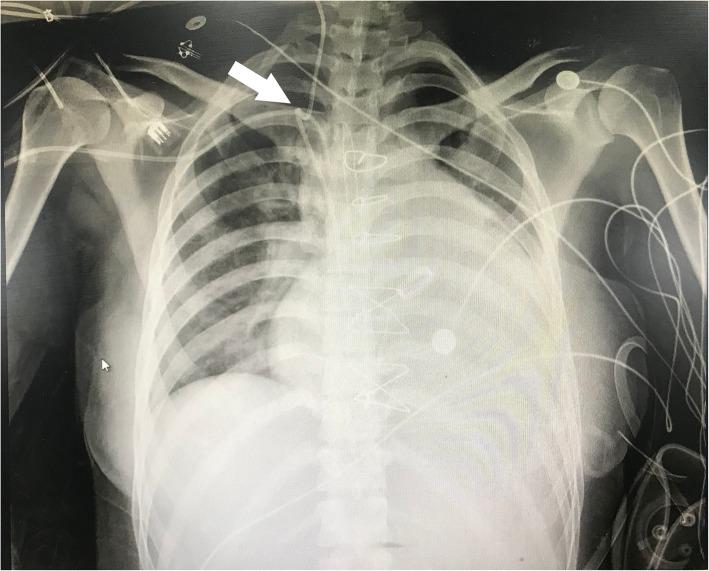

拔除困难:一根 Swan-Ganz 导管盘绕在中心静脉导管上。

Difficult removal: a Swan-Ganz catheter coiled on the central venous catheter.

This case presents the difficult removal of a Swan-Ganz catheter in a 28-year-old female patient after cardiac surgery. Fluoroscopy and chest X-ray revealed that a portion of the Swan-Ganz catheter was coiled on the central venous catheter at the level of the superior vena cava. Under X-ray guidance, the central venous catheter was first removed, and then the Swan-Ganz catheter was successfully withdrawn through the percutaneous introducer sheath.

本病例呈现了一名28岁女性患者心脏手术后Swan-Ganz导管拔除困难的情况。荧光镜检查和胸部X线显示,Swan-Ganz导管的一部分在上腔静脉水平盘绕在中心静脉导管上。在X线引导下,首先拔除中心静脉导管,然后通过经皮导入鞘成功拔出Swan-Ganz导管。